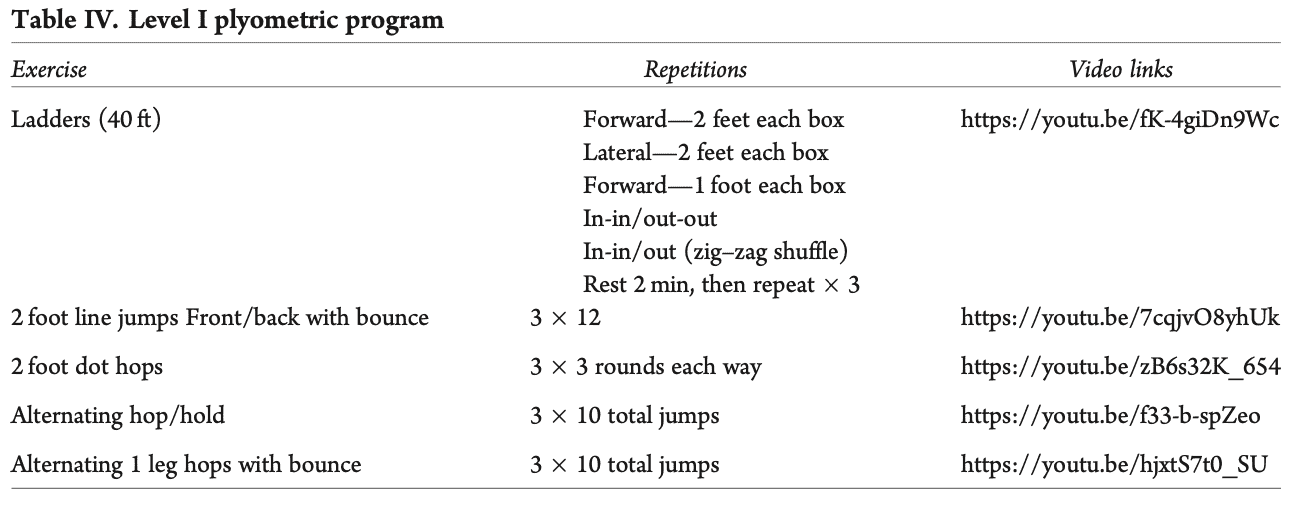

- 第二阶段是快速反应和负重活动。 他们声明如下 "快速肌肉反应和负重练习在这一阶段开始,单腿和双腿之间的接触次数约为 500-600 次。 因此,如果跑步者的平均步频为 170-180 步/分钟,那么需要跑 5-7 分钟才能达到必要的 500-600 次单脚接触"。